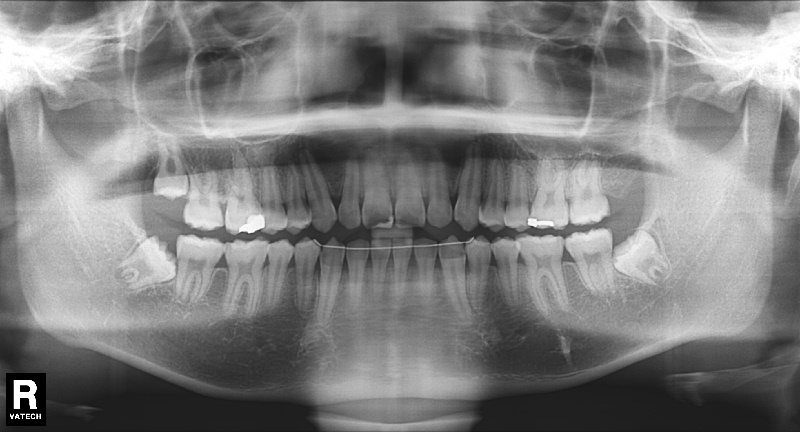

치료 후 사진입니다.